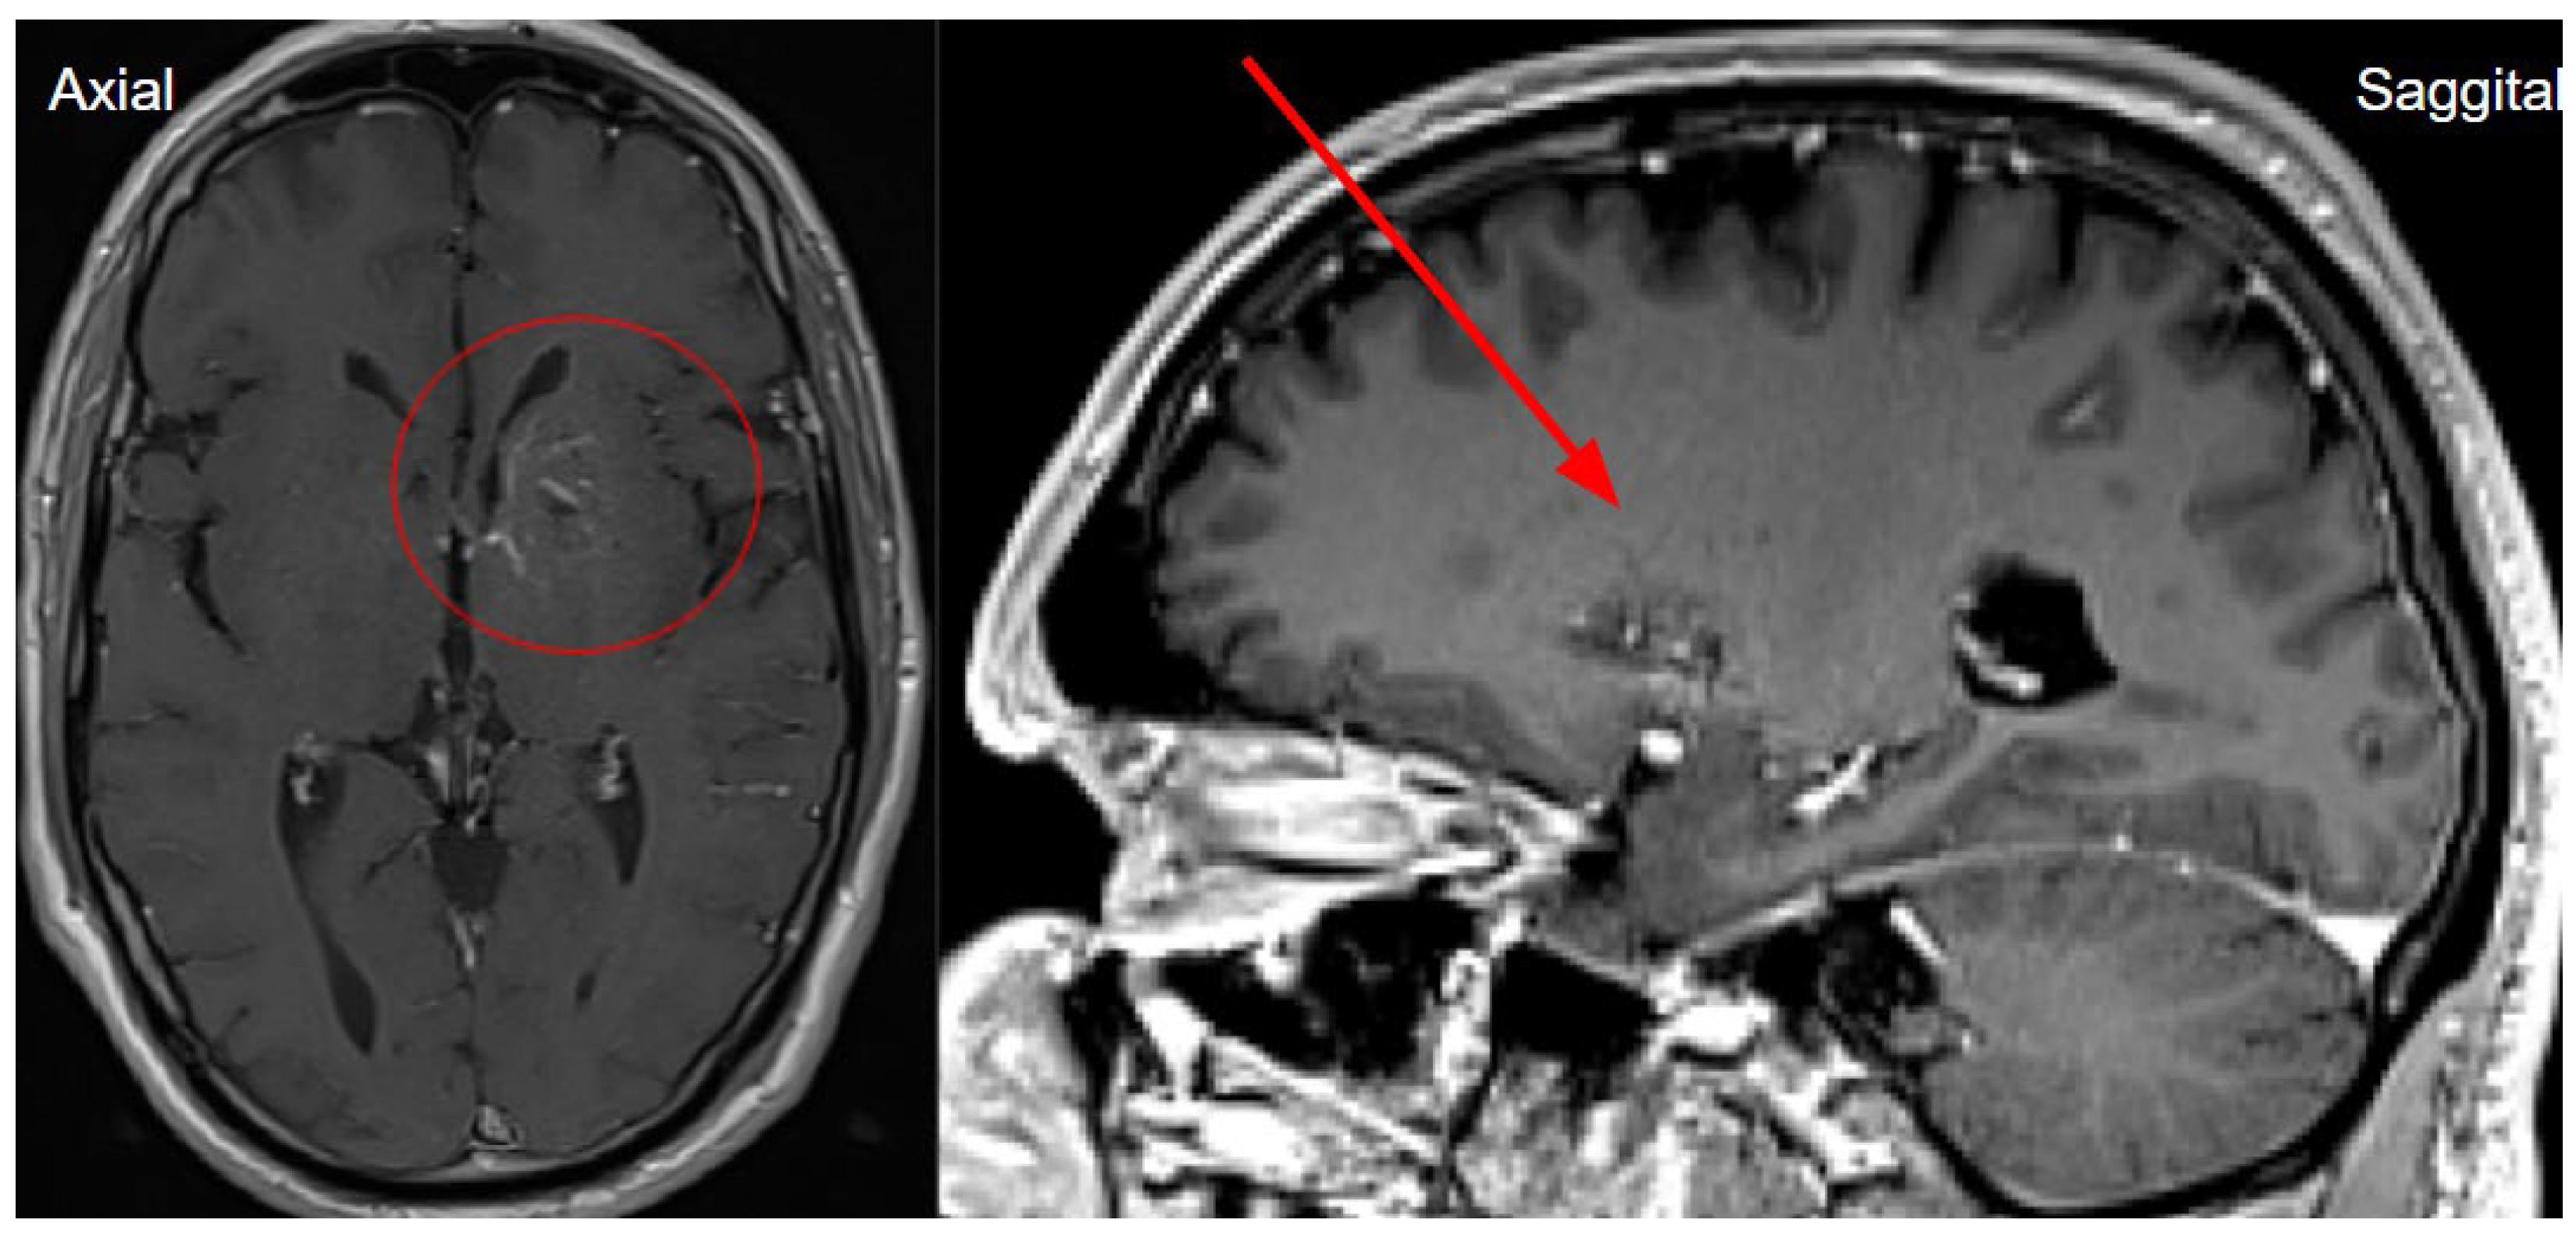

Figure 3. Computed tomography post contrast on left basal ganglia level in axial and sagittal planes showing a low contrast enhancement vessel- venous angioma, which corresponds to developmental venous anomaly (DVA), which we think is the causative agent for basal ganglia calcinosis (red circle and red arrow).

The next day, a neuroradiologist reviewed a control followup NECT, that demonstrated an ischemic lesion localized to the left insula, predominantly involving the left parietal lobe and the superior gyrus of the left temporal lobe (Figure 1). Additional radiological findings included a hyperdense artery sign, characteristic of acute thrombosis, and basal ganglia calcification on the left side, warranting further investigation to clarify the underlying aetiology. Subsequently MRI of the brain was conducted, which also revealed ischemic signs, as well as unilateral basal ganglia calcification (Figure 6). Digital subtraction angiography (DSA) was performed to clarify reasons for unilateral basal ganglia calcifications, and it confirmed the presence of a developmental venous anomaly (Figure 7).